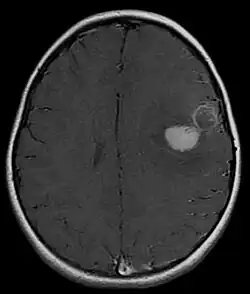

Several analysis can be used to determine the presence of the disease. Physical examinations showing papilledema, visual field defects, cranial nerves palsy, dysphasia, and focal neurological deficits are evidences for possible tumor.[2] PNETs can also be spotted through computed tomography (CT) and magnetic resonance imaging (MRI).[2] In images produced by MRIs, an irregular augmentation among a solid mass will indicated the presence of tumor.[3] However, the results of MRIs are usually ambiguous in defining the presence for this specific tumor.[2] In CT scans, the presence of PNETs will be indicated by an elevated density and an increase in volume of the brain.[2] The CT scan can also show calcification,[3] which is present in 41-44% of PNET cases.[2] Since the tumor can be replicated in other parts of the nervous system through the cerebrospinal fluid (CSF), a CSF analysis can also be conducted.[2] A spinal MRI is a fourth type of analysis that is useful in investigating the level of tumor propagation to the spinal cord.[2]

A method for eliminating tumorous mass is surgery, where the best outcome would be total resection, meaning the complete removal of the tumor.[2] Along with the surgery, several measures that contribute to a safe procedure can be taken: urine exams, transfusion, and the constant supervision of arterial pressure.[2] Possible problems that arise from the surgery include hemorrhage, brain edema, and hemiparesis.[2] MRIs are typically done after 1 or 2 days of postoperative in order to inspect the amount of tumor remaining.[2]